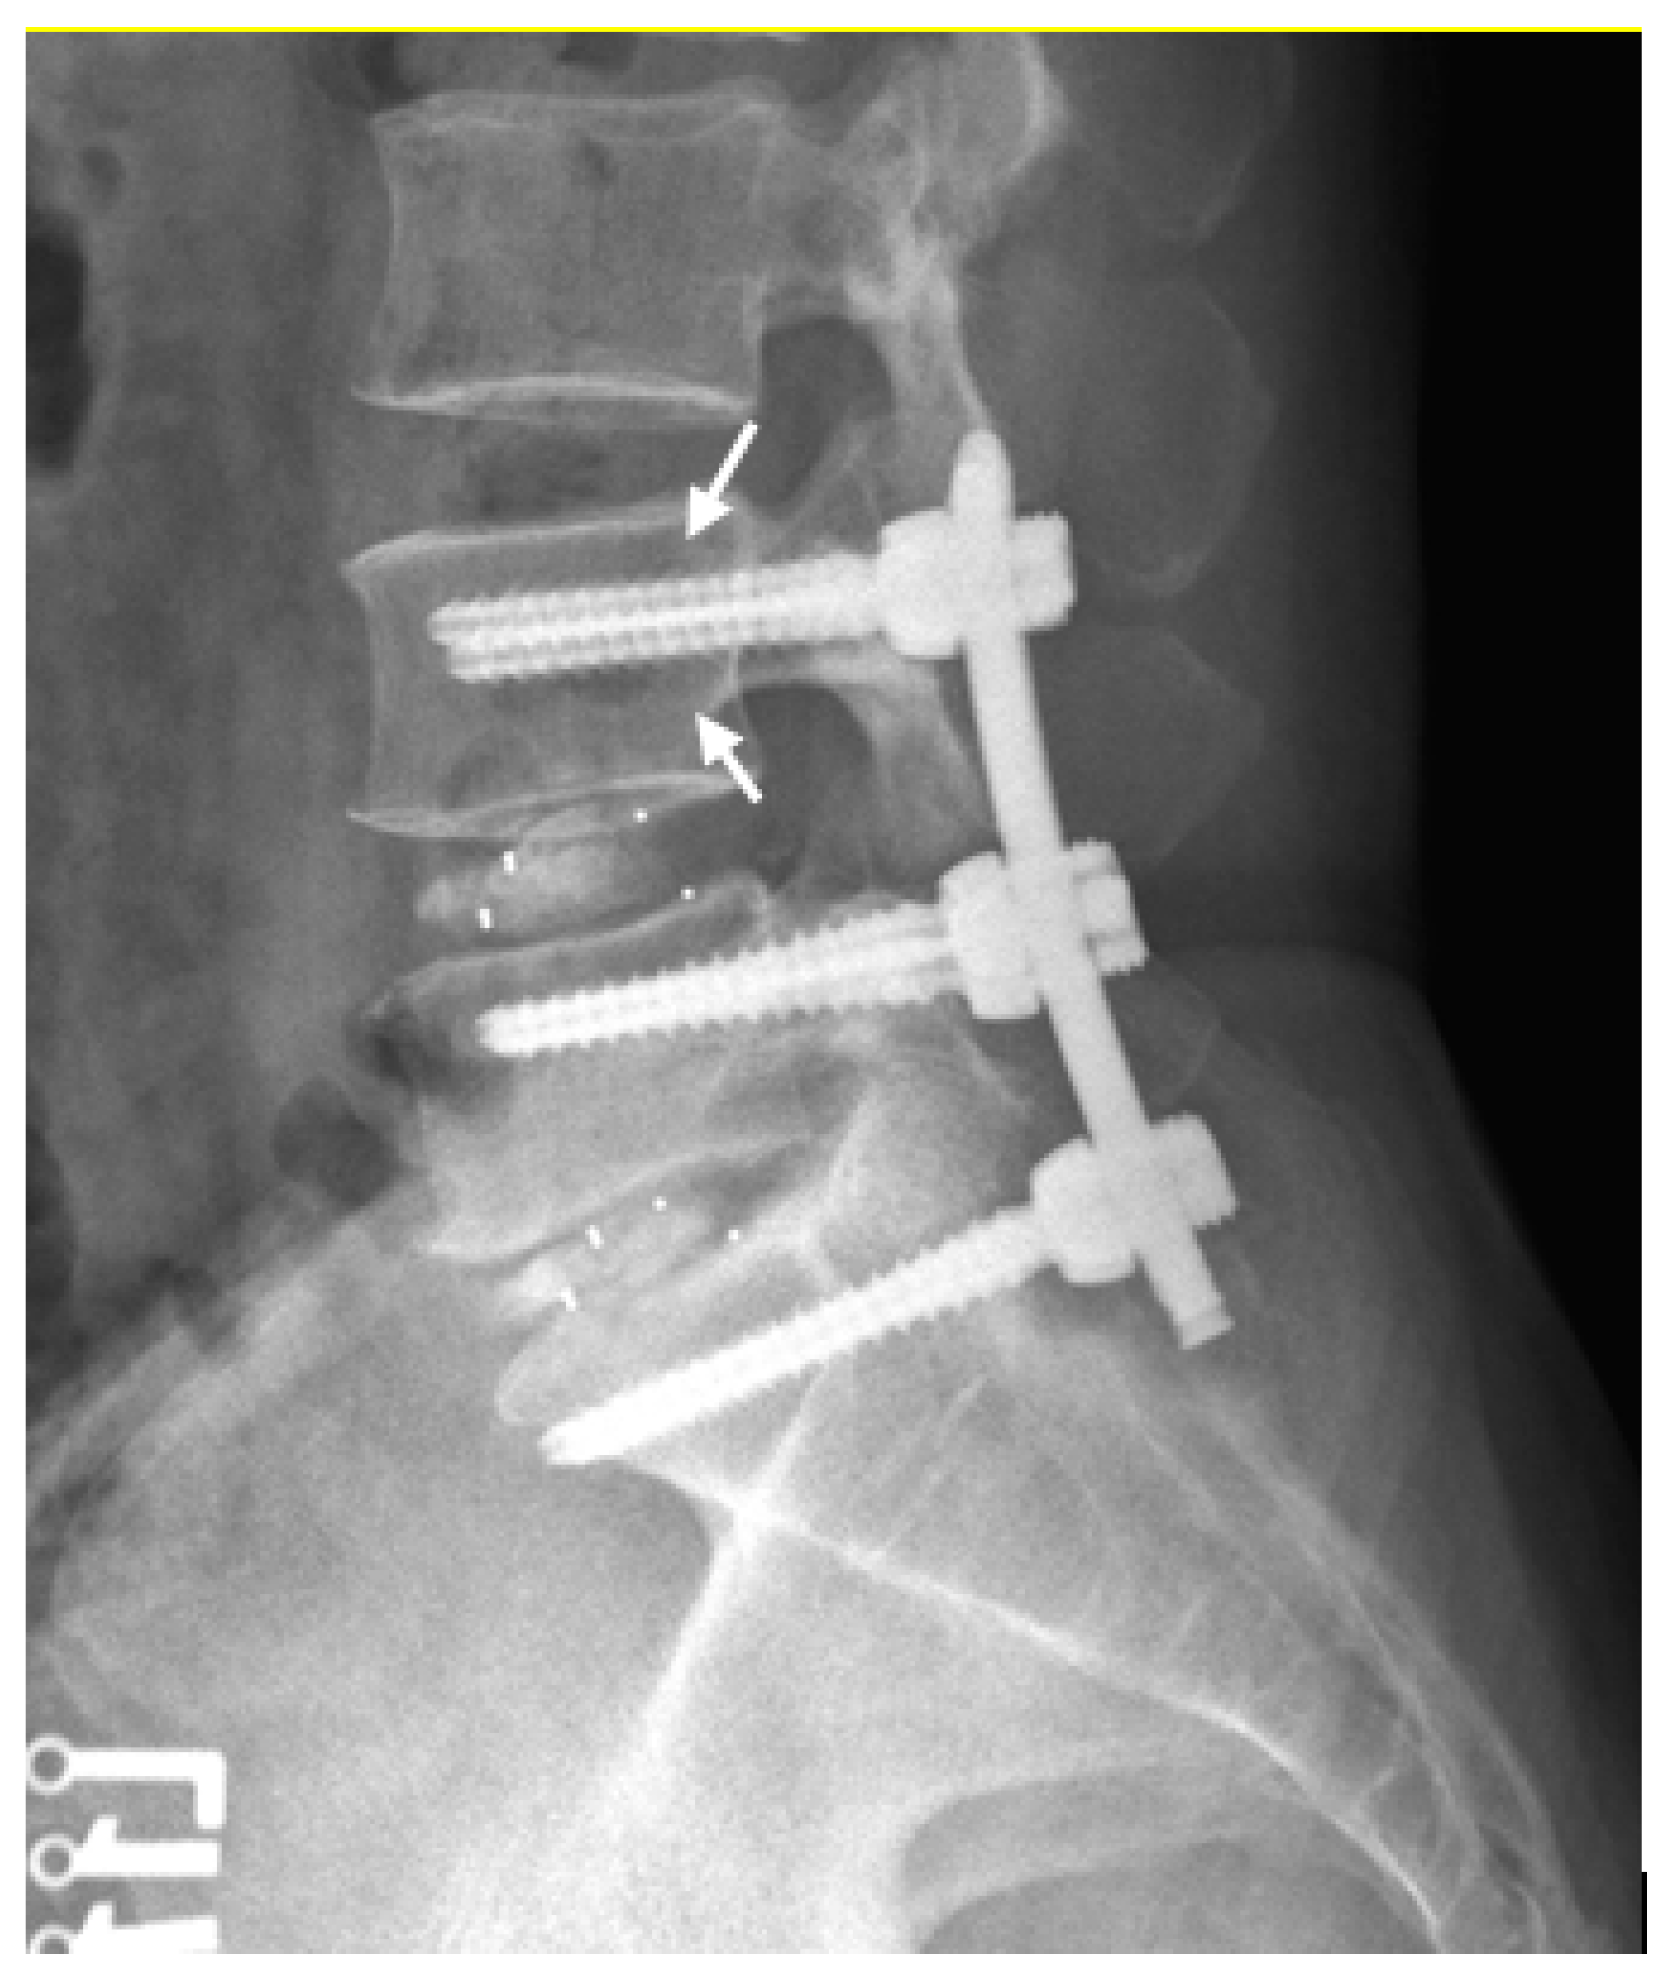

2.4. Measurements of Radiographic Parameters

2.5. Definition of Screw Loosening and Cage Subsidence